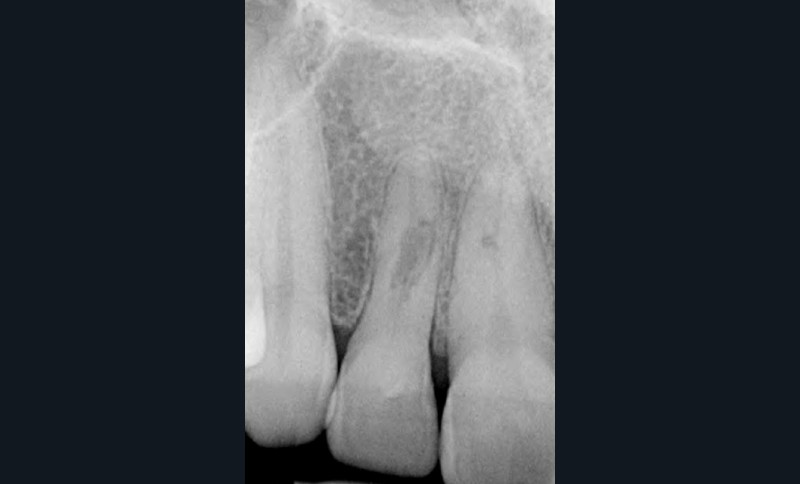

Si l’étude de Peters [18] nous montre que l’instrumentation laisse 35 % du volume canalaire non instrumenté, Ricucci et Siqueira montrent que la préparation physico-chimique n’élimine que partiellement les tissus nécrotiques à l’entrée des canaux latéraux, des isthmes et des ramifications apicales, en laissant des tissus enflammés et infectés, en association avec des lésions apicales [29] (fig. 4 et 5).

Fig. 4 – Coupe d’une racine mésiale de molaire mandibulaire avec deux canaux traités. Coupe à 3 mm de l’apex, coloration Brown et Brenn, technique modifiée par Taylor. Ces images montrent un isthme étroit avec une infection bactérienne, ce qui prouve l’importance de désinfecter et d’inclure l’isthme dans les traitements conventionnels et dans les rétropréparations apicales en chirurgie endodontique.